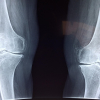

¡Conviértete en un experto en Interpretación de imágenes radiológicas con nuestro curso en línea! Aprende a identificar patologías, lesiones y anomalías a través de radiografías, tomografías y resonancias magnéticas. Mejora tus habilidades en radiología y destaca en el campo de la medicina. ¡Inscríbete ahora y lleva tu carrera al siguiente nivel!

Lección 1 - Interpretación de imágenes de huesos